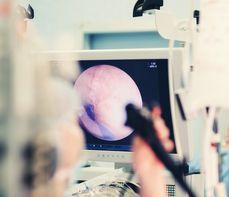

Kalprotektyna w diagnostyce raka jelita grubego

Choć kalprotektyna nie jest specyficznym markerem nowotworowym, jej wysokie stężenie może wskazywać na obecność raka lub innej poważnej patologii w jelicie grubym. Jej główne zastosowania w kontekście raka jelita grubego to:

- wczesna selekcja pacjentów do kolonoskopii – u pacjentów z objawami alarmującymi (np. krwawienie, anemia) kalprotektyna może pomóc zidentyfikować tych, którzy wymagają pilnej diagnostyki;

- wysoka wartość predykcyjna ujemna (NPV) – niskie stężenie kalprotektyny (<50 µg/g) pozwala z dużym prawdopodobieństwem wykluczyć nowotwór lub aktywny stan zapalny;

- wsparcie w ocenie skuteczności leczenia – u pacjentów z nowotworem wykrytym we wczesnym stadium, kalprotektyna może być pomocna w monitorowaniu odpowiedzi na leczenie.

Kalprotektyna w kale to obiecujący biomarker, który znajduje coraz szersze zastosowanie w diagnostyce raka jelita grubego. Szybkie testy immunochromatograficzne i ilościowe pozwalają na wczesną ocenę ryzyka i mogą przyczynić się do wcześniejszego wykrycia nowotworu. Choć nie zastępują one kolonoskopii, stanowią cenne narzędzie w rękach lekarza pierwszego kontaktu.